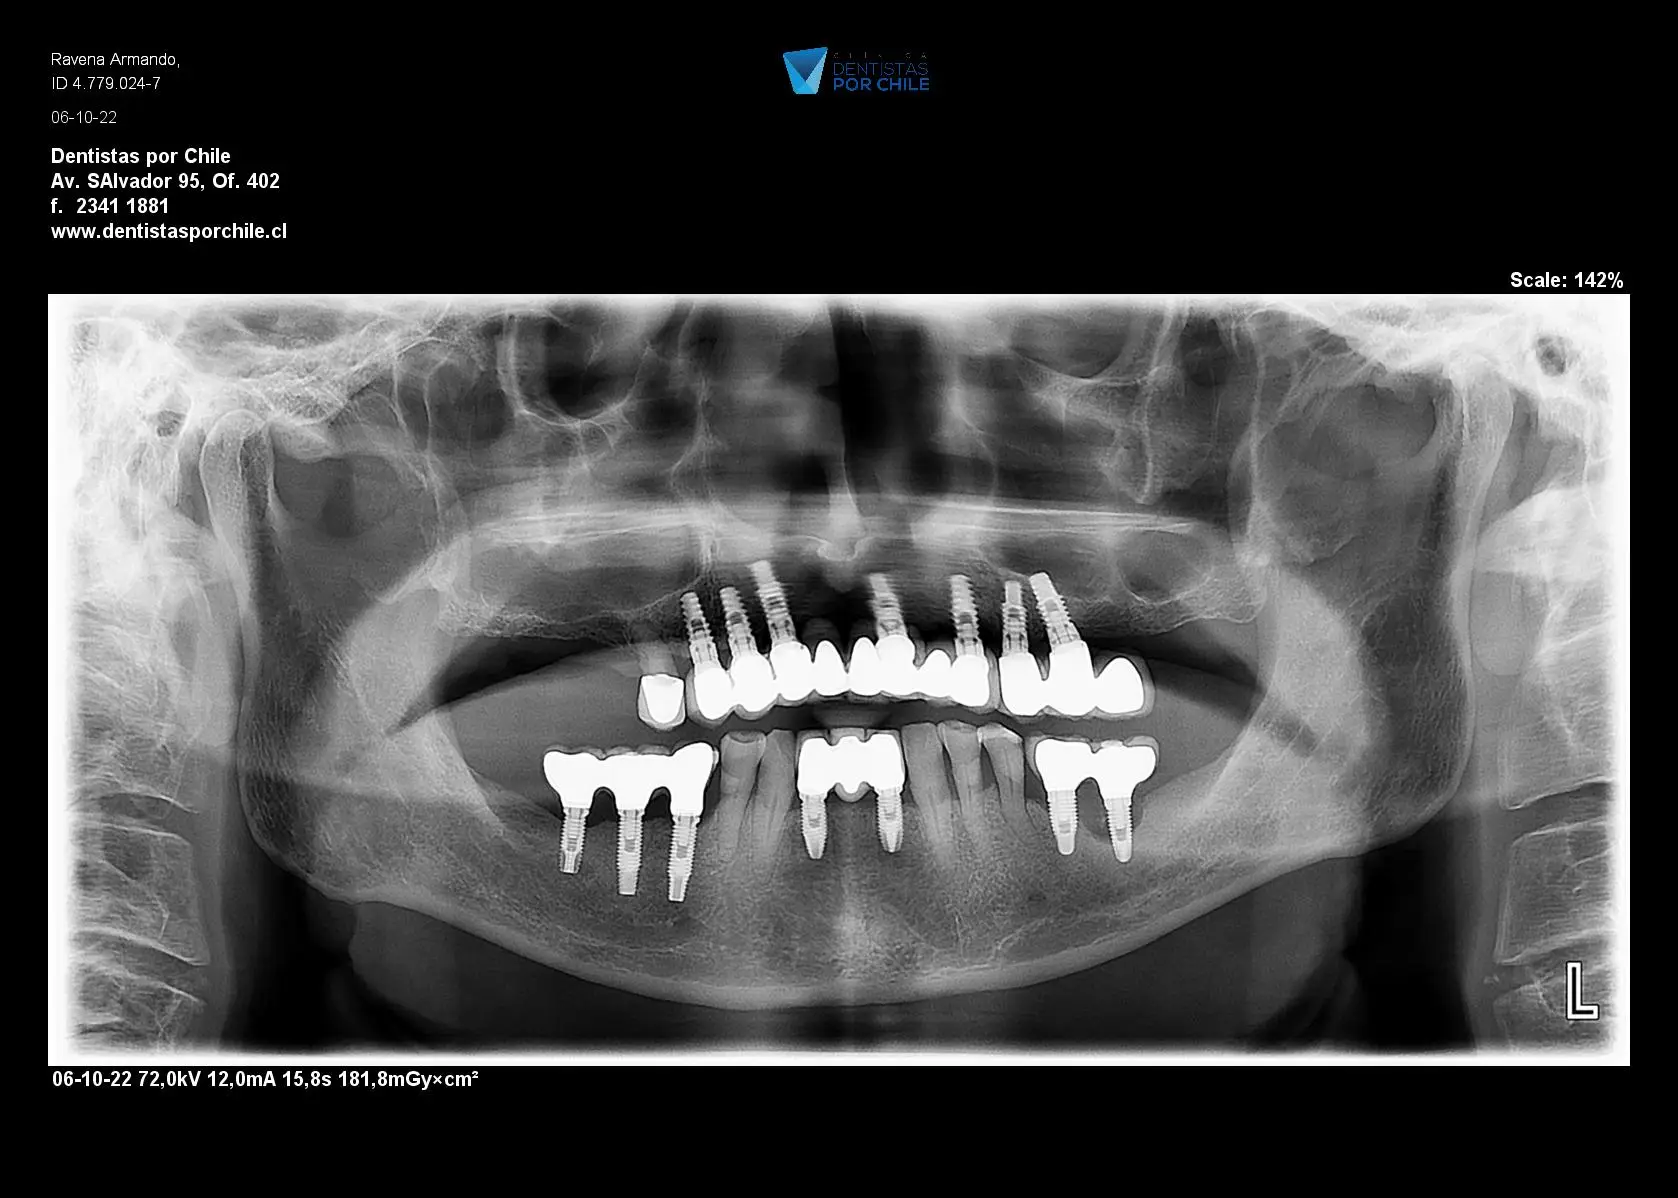

El proceso de colocación de implantes comienza con una evaluación completa. El Dr. Julio Guerra, junto con su equipo en la Clínica Dentistas por Chile, realiza un análisis detallado de la salud bucal del paciente, incluyendo radiografías y modelos 3D, para planificar la colocación precisa de los implantes.

El Dr. Julio Guerra utiliza técnicas avanzadas para colocar implantes en el maxilar superior, asegurando una integración ósea adecuada y un ajuste perfecto de la prótesis final. Esto incluye el uso de guías quirúrgicas y tecnología de imagen para una colocación precisa.

Resultados antes y después

Las imágenes de antes y después muestran claramente la mejora estética y funcional lograda con los implantes dentales, demostrando la eficacia del tratamiento.